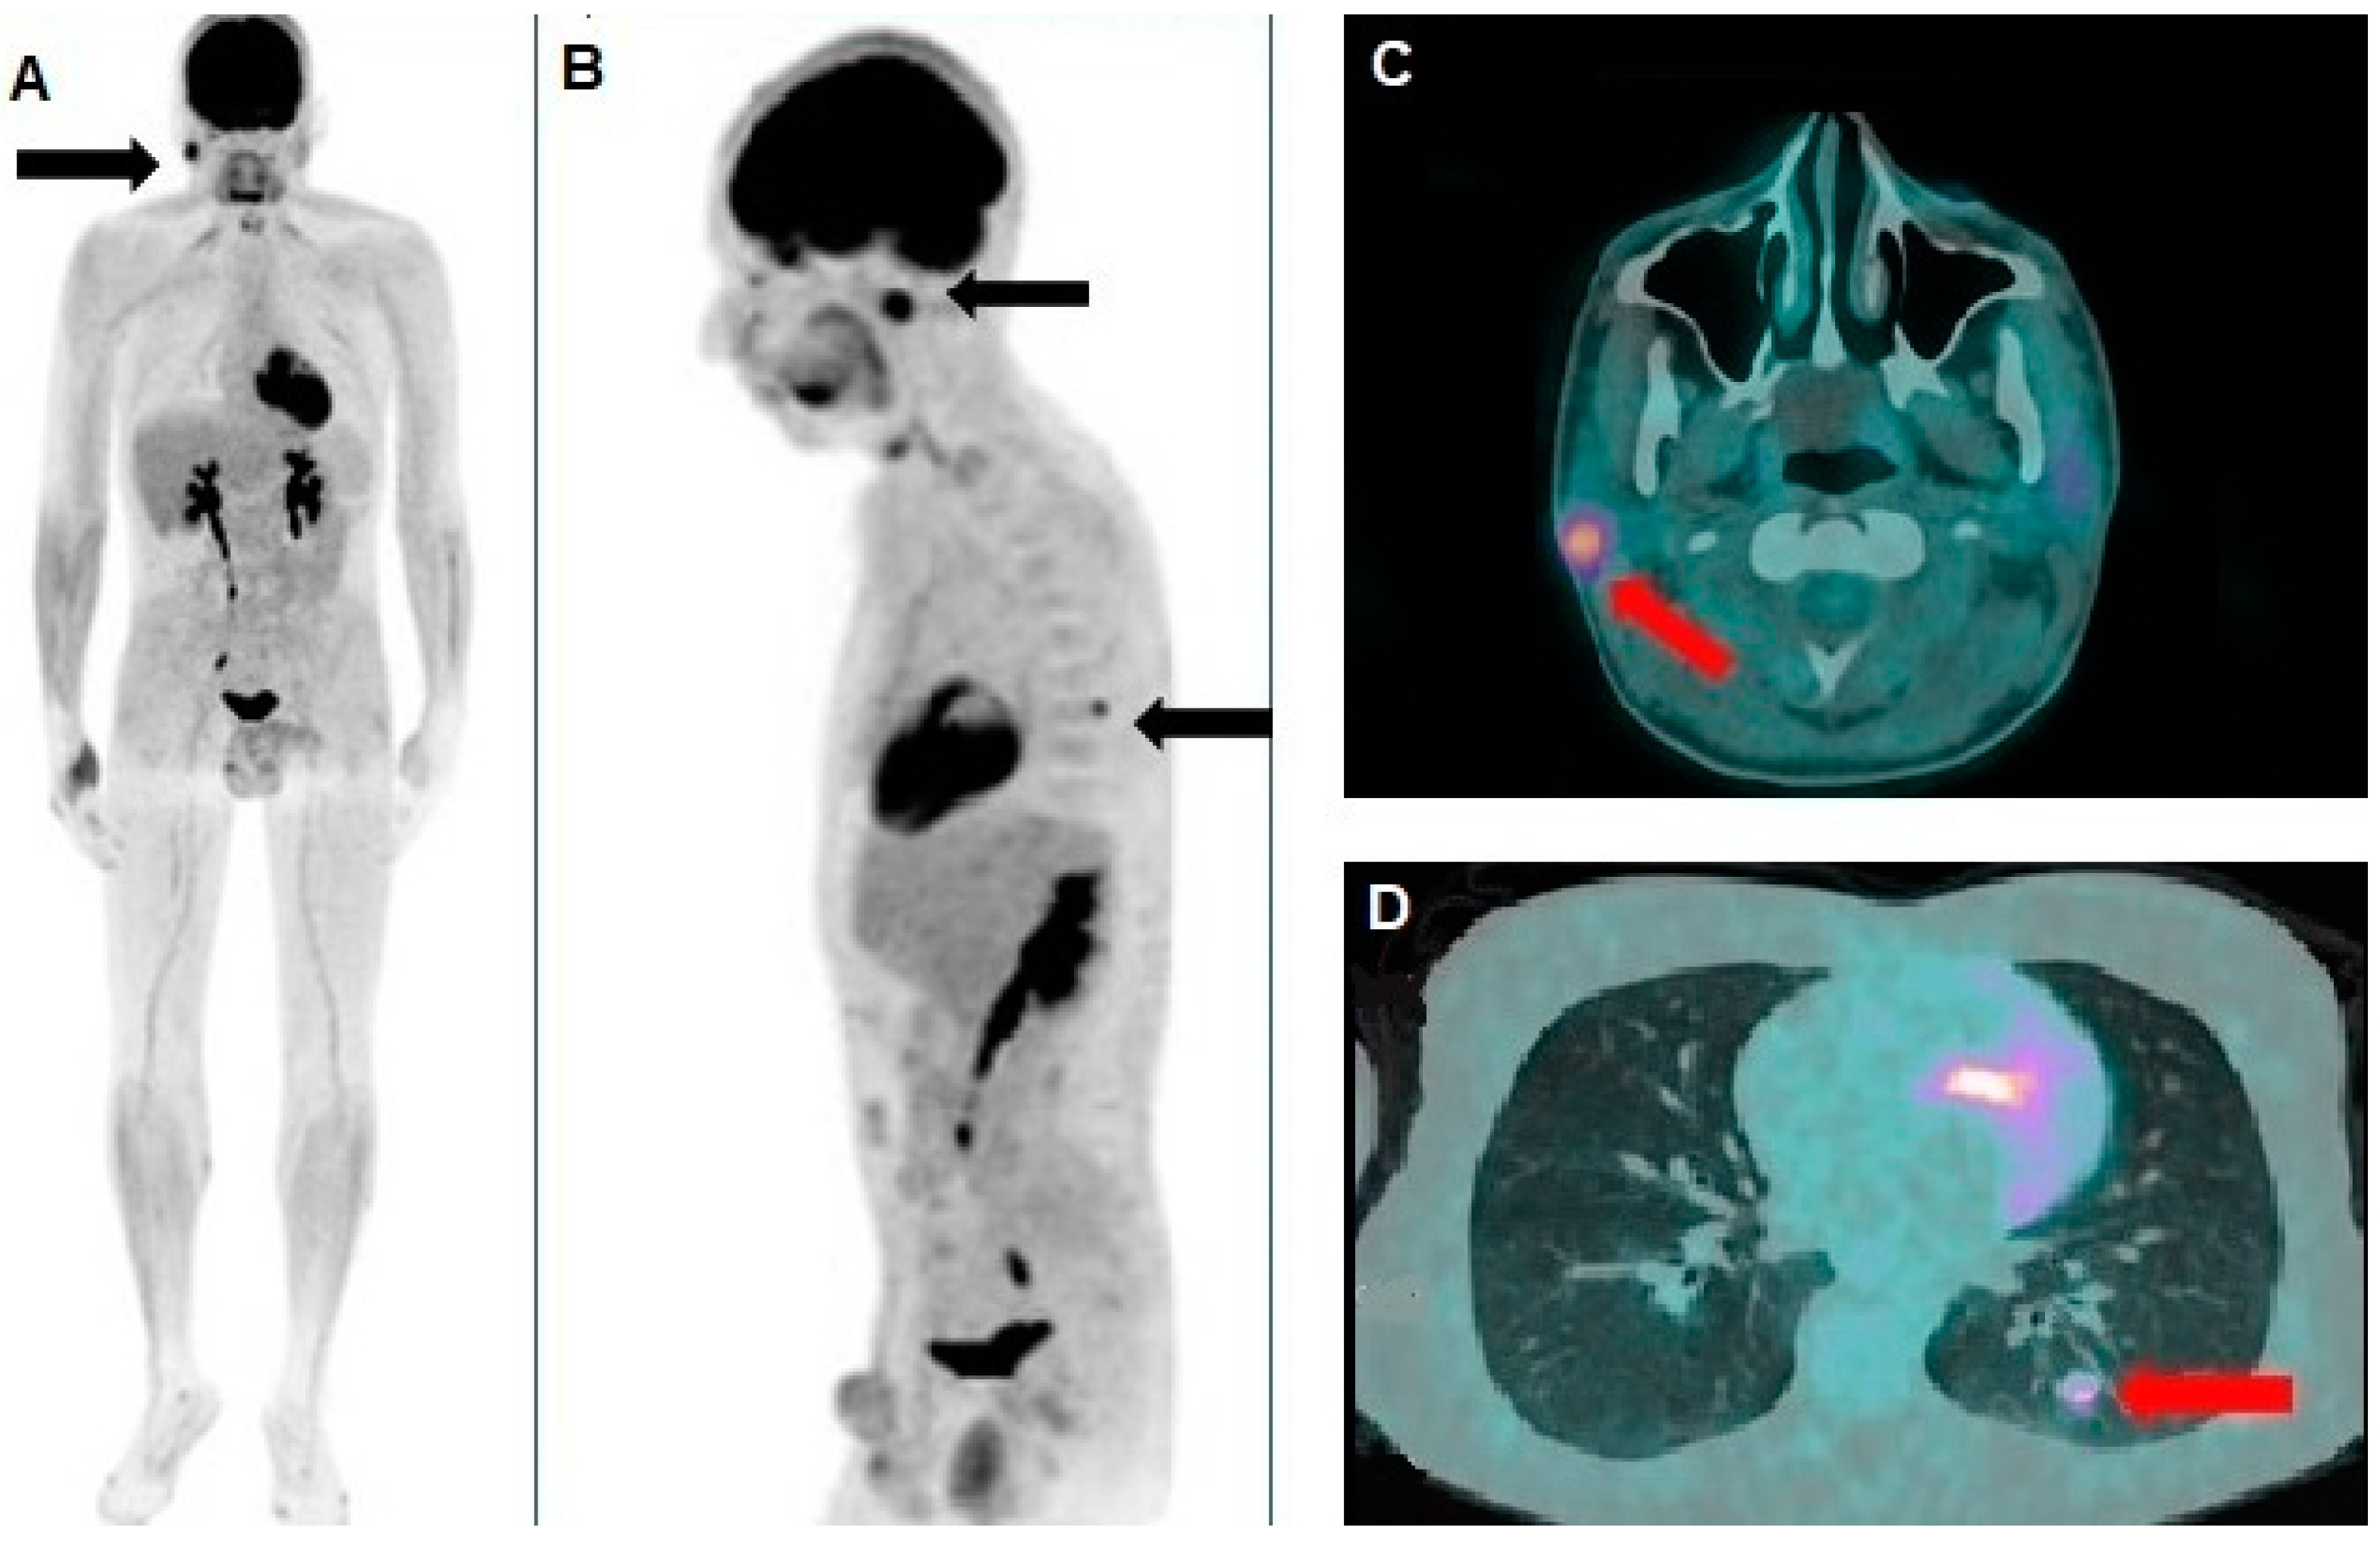

A Rare Case of Xeroderma Pigmentosum: Nivolumab Treatment for Three Cutaneous Malignancies with Clinical and Metabolic Imaging Correlation

Proietti, I.; Pirisino, R.; Azzella, G.; Coppolelli, V.; Greco, M.E.; Casciani, E.; Potenza, C.; Filippi, L. A Rare Case of Xeroderma Pigmentosum: Nivolumab Treatment for Three Cutaneous Malignancies with Clinical and Metabolic Imaging Correlation. Diagnostics 2025, 15, 979. https://doi.org/10.3390/diagnostics15080979